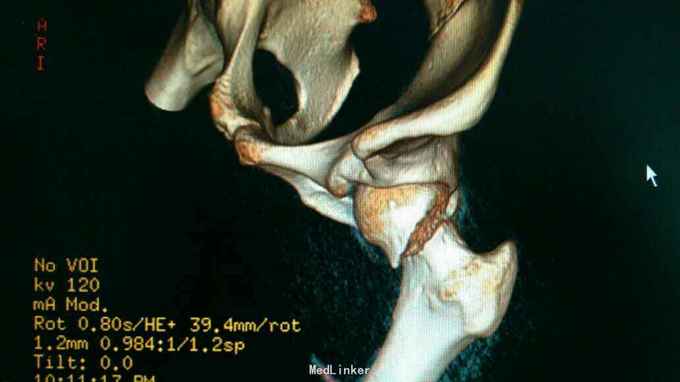

24岁男性,运动中摔倒致左髋疼痛活动受限,

左髋部压痛,大粗隆扣痛,下肢杆力消失,x光及CT证实左股骨颈骨折